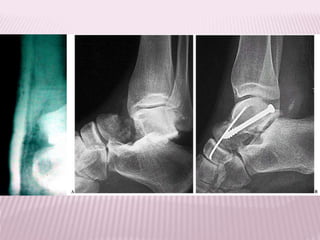

FRACTURA DE TOBILLO

 Corresponden al grupo de lesiones

traumáticas quizás más frecuentes de la vida

diaria;

 Se clasifica según Danis-Weber

Infrasindesmóticas

(sindesmosis

indemne)

Transindesmoticas solo

lesión de la

sindesmosis

Suprasindesmoticas lesión de

sisdesmosis y membrana

intereósea

50% reparación quirúrgica

 Fractura unimaleolar Fractura bimaleoar

Trimaleolar

* Dolor espontáneo, generalmente intenso; se exacerba con los movimientos

o tentativas de caminar

* Aumento de volumen, rápido en aparecer y progresivo.

* Equímosis tardías, submaleolares y que a veces descienden a lo largo de

los bordes externo o interno del pie.

* Impotencia funcional.

TRATAMIENTO

Radiografía de una fractura de tobillo tratada

quirúrgicamente con placa y tornillos de

titanio.

Osteosíntesis: Produce un alto grado de

estabilidad mecánica.